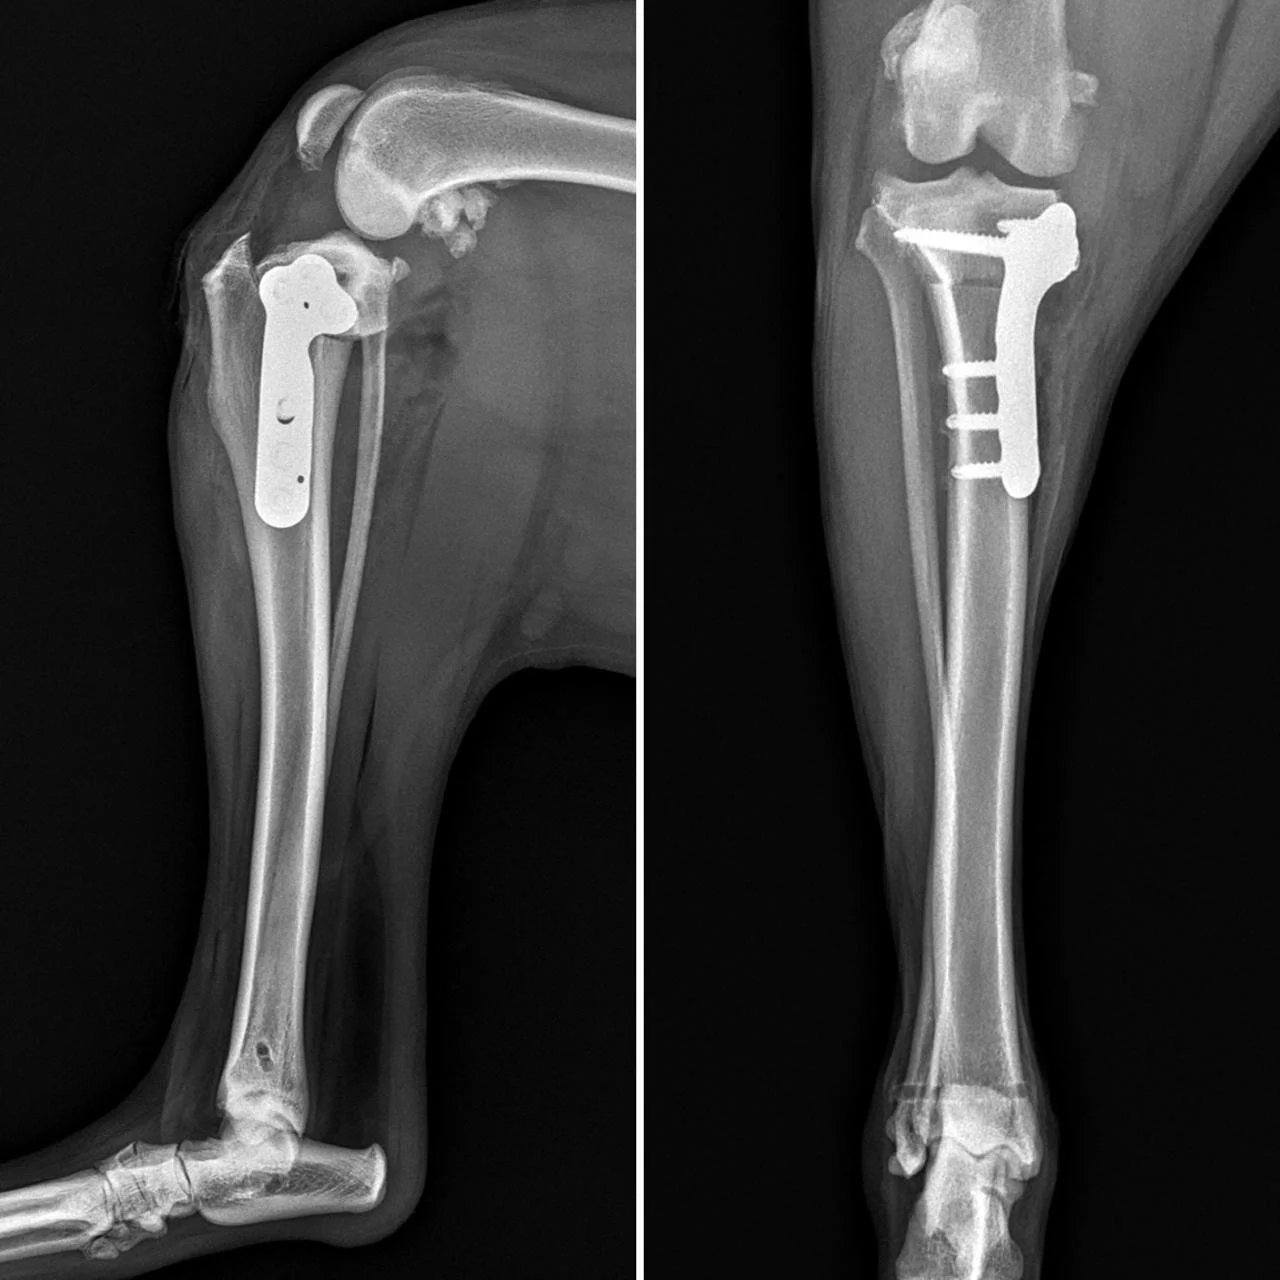

Keysha’s story has been a rollercoaster for everyone involved. After months of training alongside her handler Tamara, their fieldwork hit a series of unexpected hurdles. First, Tamara fractured her foot. Then Keysha suffered a leg injury, followed by a heartworm diagnosis. Just as she recovered, she faced two more setbacks - back-to-back surgeries for torn cruciate ligaments.

In total, Keysha spent seven months out of action in 2024. But she came back stronger than ever.